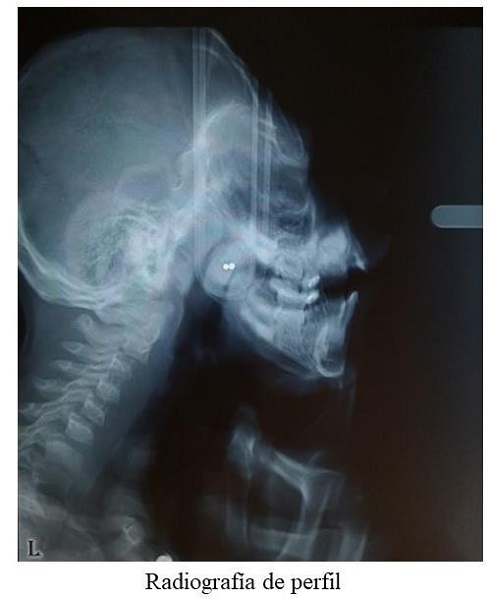

Se solicitaron apoyos diagnósticos tipo radiografía de perfil. El padre sostuvo la cabeza del niño para realizar el examen debido a, cómo podía esperarse por la cuadriparesia espástica, no había sostén cefálico. No fue posible analizar el tamaño ni la posición de los maxilares (figura 4).